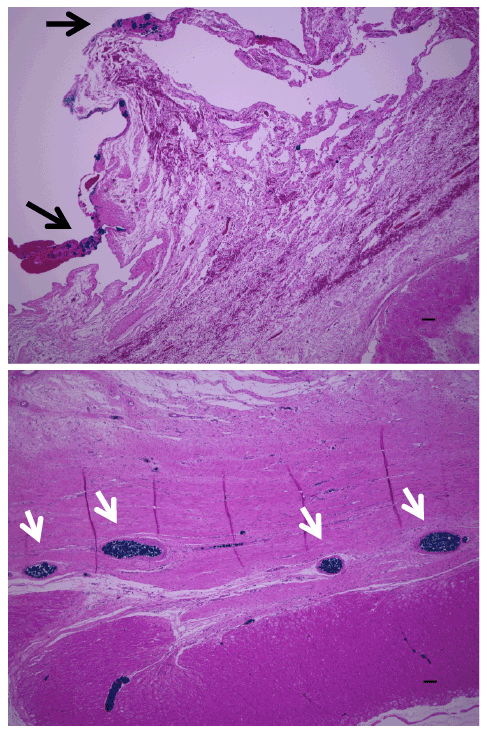

| Figure 6: Phthalocyanine blue was infused into the coronary artery and vascular formation was examined in the engineered myocardial tissues. Blood vessels within the cell sheet construct stained blue within the host coronary vasculature (white arrow) and the implanted cell sheet construct (black arrow). |